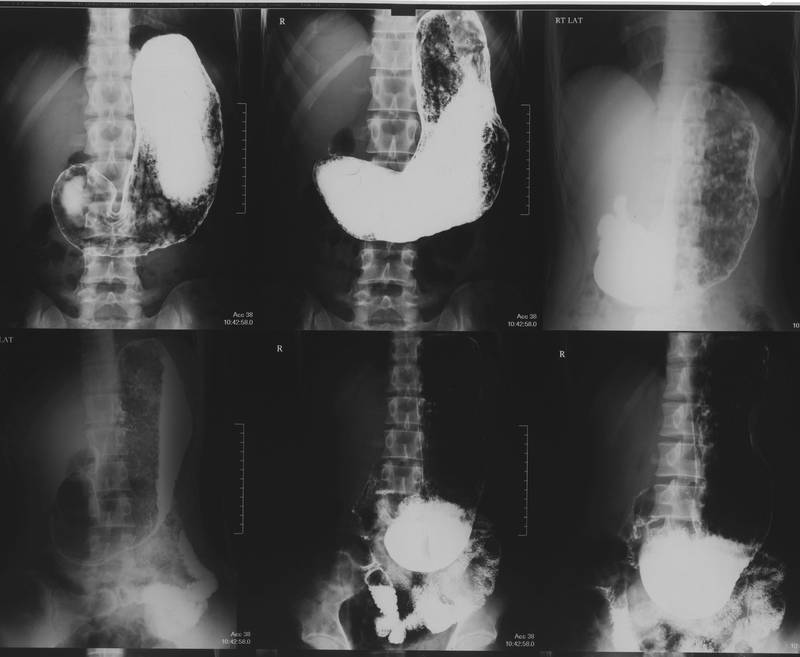

Гастроптоз на контрастной рентгенограмме